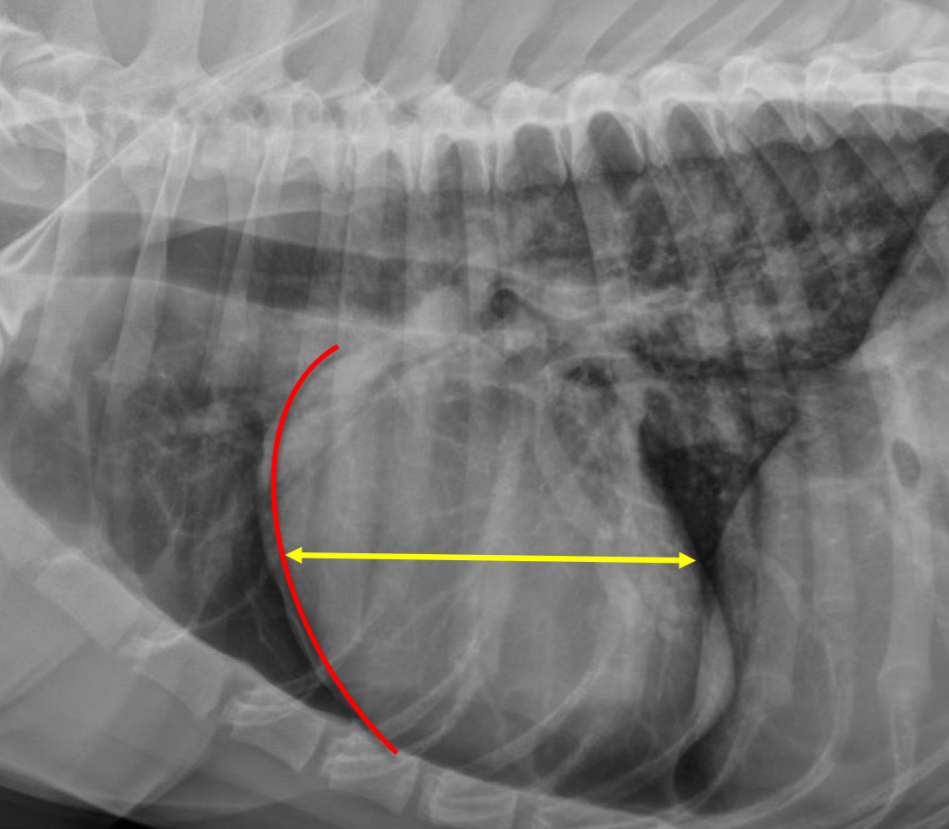

3 features of LAE on lateral

-dorsal displacement of main stem bronchi by a hunchback bump

-increased cd.dorsal cardiac border

-loss of cd.cardiac waist - straightening of cd.cardiac margin

What part of the heart is enlarged

LAE